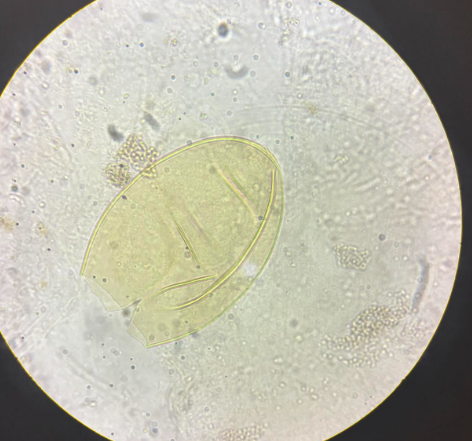

schistosoma mansoni jajo

schistosoma haematobium jajo

schistosoma haematobium jajo

schistosoma japonicum jajo